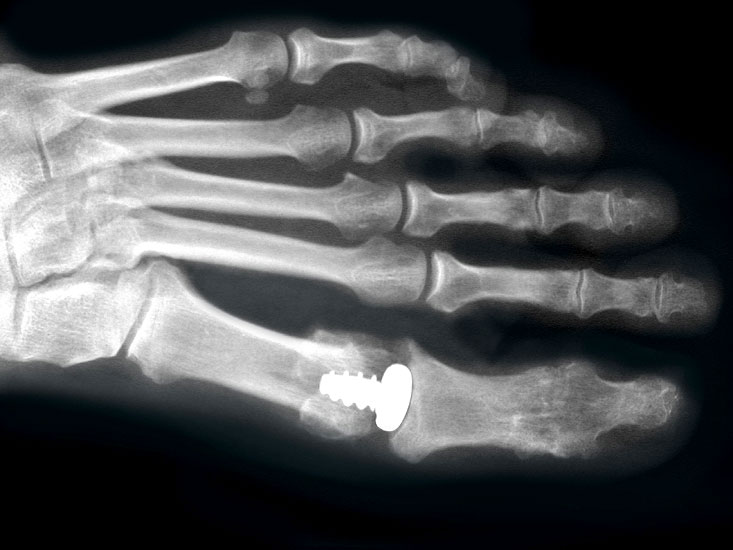

Die ersten Versuche mit der Prothetik am Großzehengrundgelenk wurden mit metallischen Hemi-Implantaten (Abb. 13, 14) vorgenommen. Eine Studie 47 mit größerem Kollektiv im Langzeitverlauf zeigte befriedigende Resultate, trotzdem hat sich die Technik bis heute nicht wirklich durchgesetzt. Der gleiche Autor verglich die Endoprothese mit der periartikulären Osteotomie und konnte keine wesentlichen Unterschiede feststellen 48. Eine neuere Studie vergleicht die Hemiarthroplastik mit der Arthrodese und der Resektionsarthroplastik und kann keine signifikanten Unterschiede feststellen 49. Metall–Polyäthylen-Paarungen zeigten eine hohe Lockerungsrate der Komponenten, weshalb sich diese Paarung ebenfalls nicht durchsetzte 505152. Am meisten Erfahrung besteht mit der Silikonprothese. Initial als Hemiprothese propagiert 46, wurde wegen mangelhaften Erfolgen 5354 die Totalprothese mit zwei Schäften eingeführt 55. Die Langzeitergebnisse sind widersprüchlich 55565758 so dass wegen der Verunsicherung dieses Model aktuell nicht regelmässig zum Einsatz kommt.